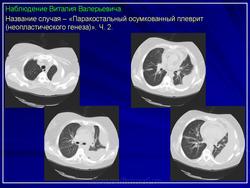

2. Осумкованный паракостальный плеврит.

ОСУМКОВАННЫЕ ПЛЕВРИТЫ.

Выраженная тенденция плевральных листков к развитию слипчивого процесса объясняет значительную частоту возникновения осумкованных плевритов. Процесс осумкования, в значительной степени, зависит от образования шварт, которые формируются к концу первой недели патологического процесса.